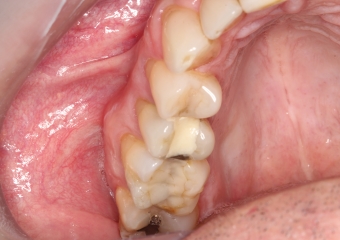

Dente definitivo